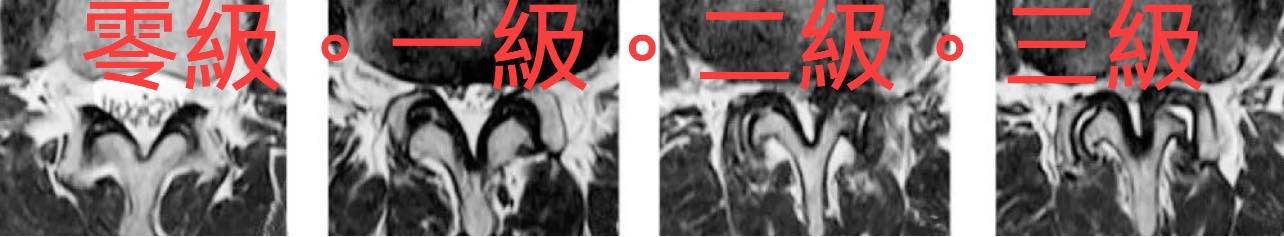

🔶根據核磁共振結果,可以看到脊椎狹窄的程度從正常到嚴重分成四級。(圖三)

☑️0級 : 無狹窄。椎管狹窄不影響硬脊膜(dura)內前方腦脊髓液 (CSF)顯影

☑️1級 : 輕度狹窄。椎管狹窄硬脊膜內看不見腦脊髓液顯影,但馬尾神經根仍清楚可見

☑️2級 : 中度狹窄。椎管狹窄硬脊膜內看不見腦脊髓液顯影,馬尾神經根也被擠壓在一起看不清分界,

☑️3 級 : 嚴重狹窄。椎管狹窄硬脊膜內看不見腦脊髓液顯影,馬尾神經根也被擠壓在一起看不清分界,硬脊膜旁邊的脂肪組織幾乎不可見。